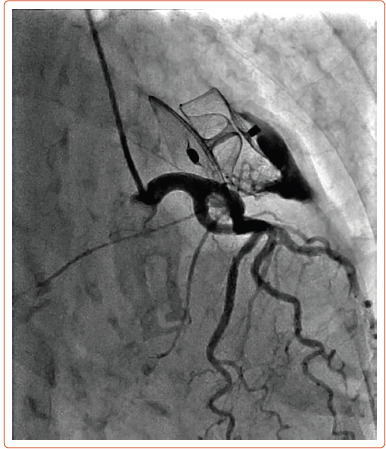

An 80-year-old patient presented with a rare complication: a late coronary-cameral fistula following implantation of an Amulet (Abbott) left atrial appendage occlusion device. Microperforations from the device's anchoring tines have previously been suggested as a possible mechanism of fistula formation, a complication reported in two other cases. We propose an alternative theory of potential collateralisation of the threatened appendage from the nearby circumflex artery.